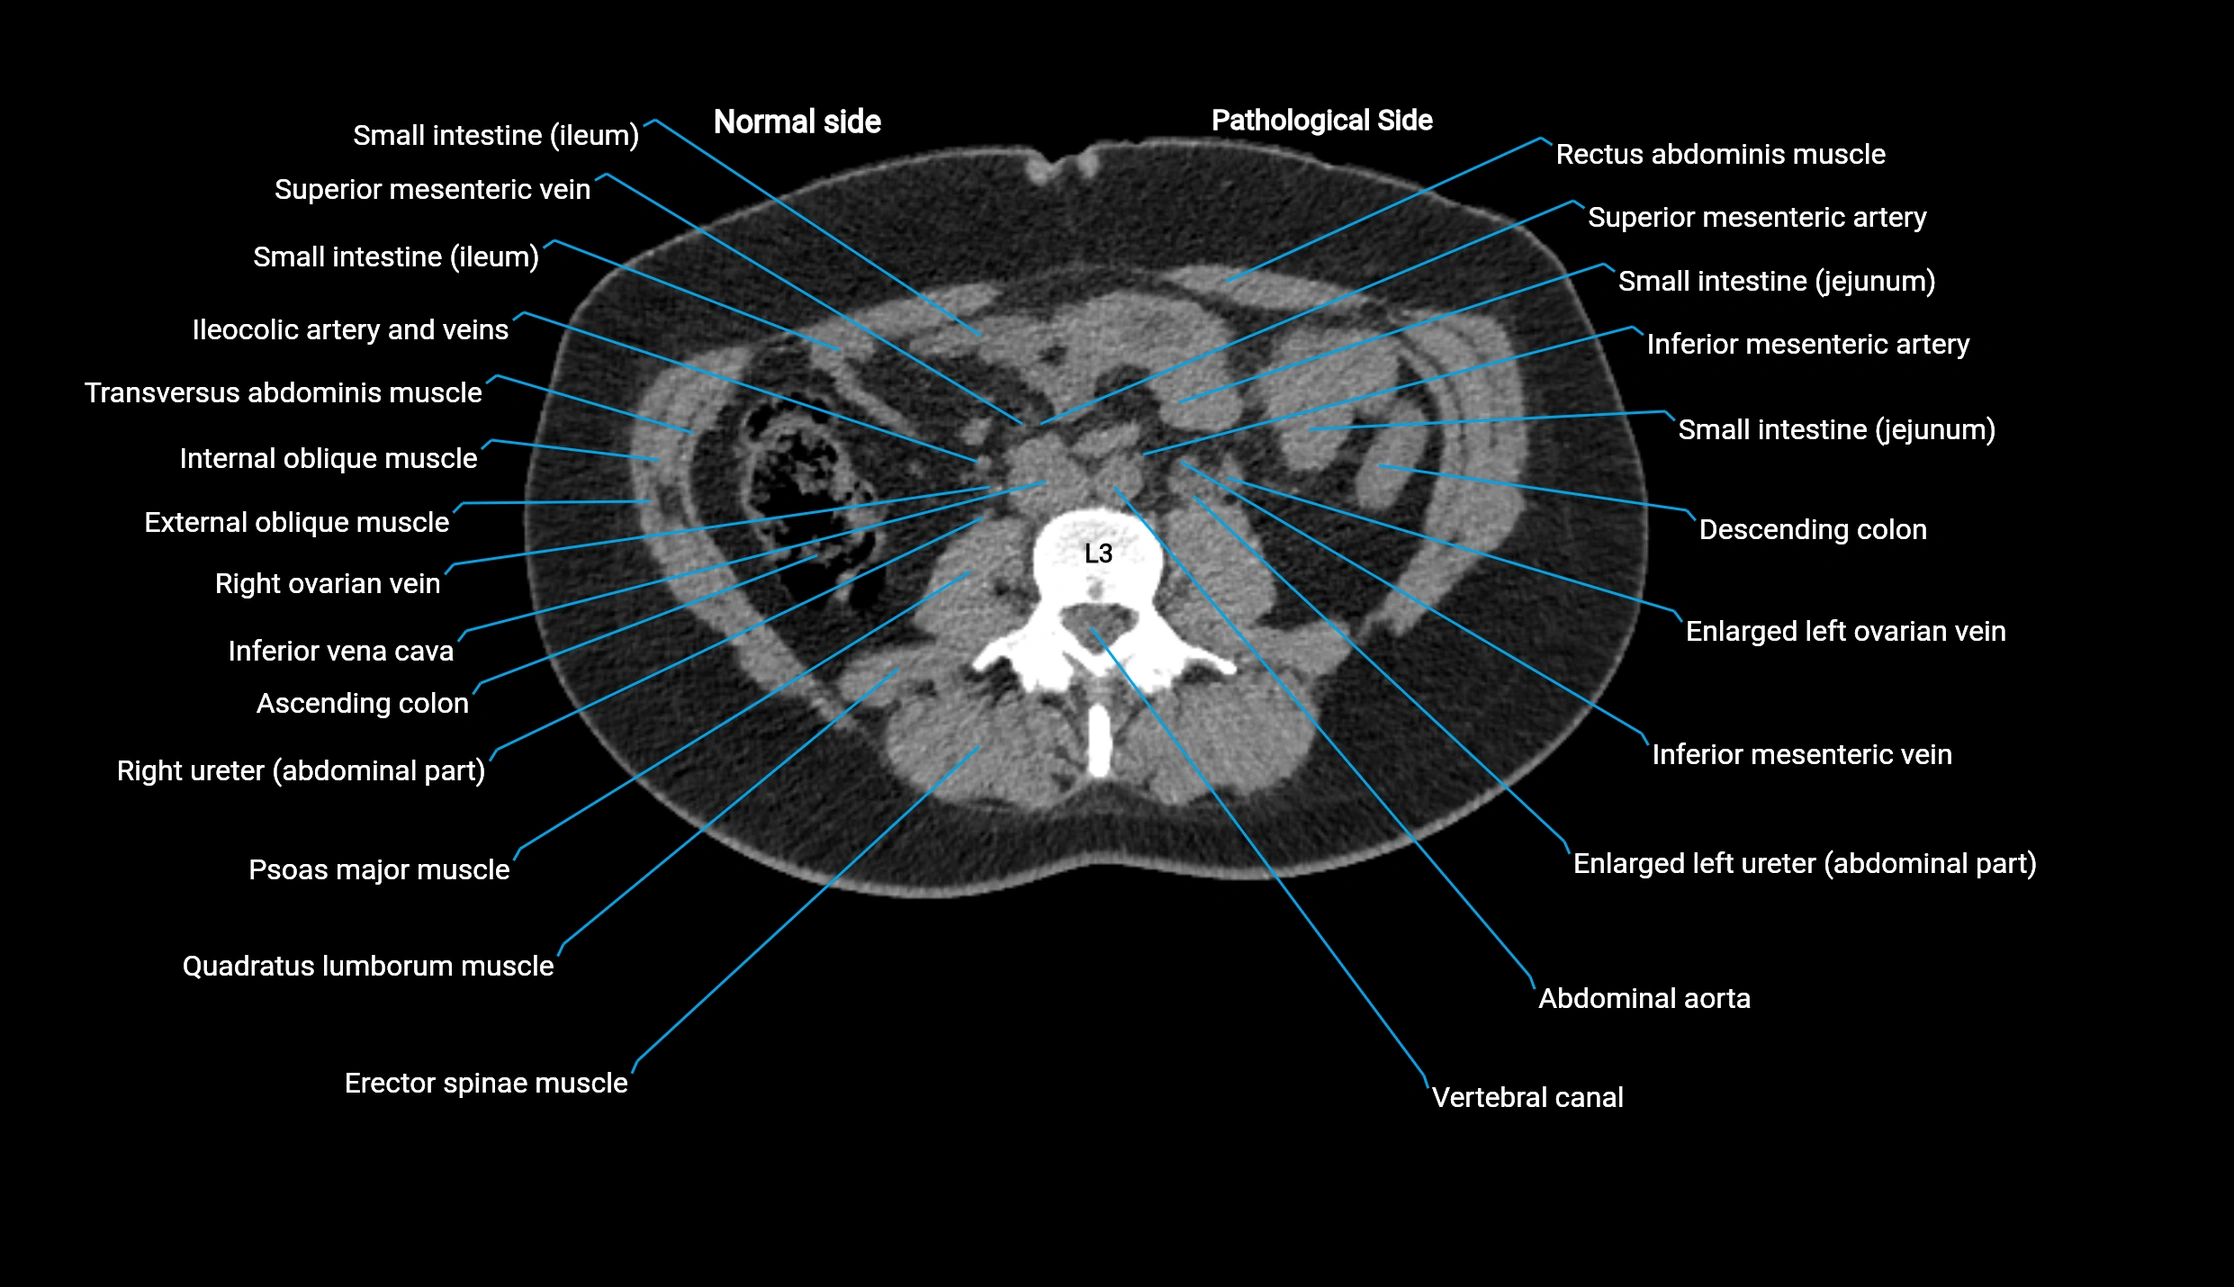

CT image

image